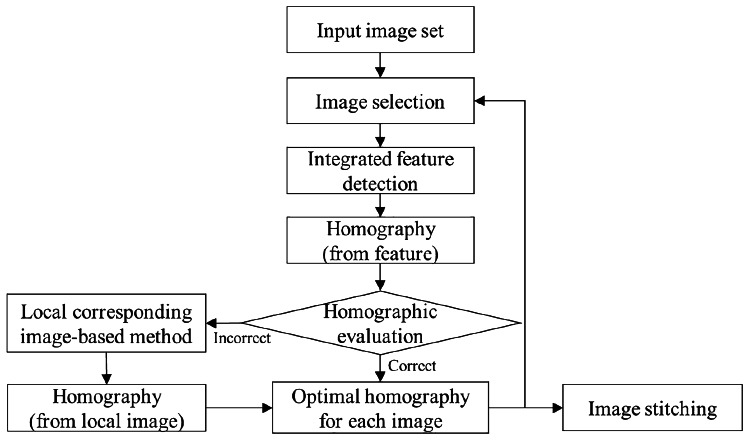

The proposed method was based on heterogeneous stitching that depends on overlap regions in X-ray images. Using integrated feature detection, homographic evaluation, and the local image-based estimation, a robust, panoramic C-arm X-ray image can be constructed. The flow of the proposed method is shown in Fig. 1. First, an image and its consecutive X-ray image were selected after the input images were arranged in order. For the selected images, the homography was estimated using the integrated feature detection. After distinct features of the images were extracted, the homography was estimated based on the matched features. The estimated homography was then verified by evaluating the homography. If the homography was correct, it was considered an optimal homography for that image and was stored. Otherwise, the local, corresponding image-based estimation was substituted for the integrated feature detection, and its homography was considered the optimal one. This process was executed iteratively until the last image in the set was processed.

Fig. 1.

Flow diagram of the proposed method for heterogeneous stitching of X-ray images by homographic evaluation